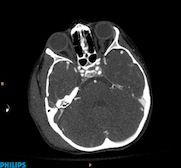

A five-year-old patient fractured the petreous bone after falling at the playground. Ingenuity CT allows low-dose evaluation of the pediatric head and neck with enhanced image quality. Scan obtained at 1.0 mSv.

Many emergency/trauma patients are young in age and could have repeated scans to monitor their progress. It is very important to be able to scan at the lowest possible radiation dose. In addition, scan protocols for emergency/trauma patients often require multi-phase scanning.

Philips Ingenuity CT provides the necessary tools, such as iDose4 iterative reconstruction technique,* and dedicated workflow to perform successful emergency and trauma CT examinations, helping to assure that emergency/trauma CT examinations are performed efficiently and are processed in a timely manner. This can allow the radiologist to provide emergency/trauma physicians and surgeons with diagnoses in the shortest possible time. This can allow the radiologist to provide emergency/trauma physicians and surgeons with diagnoses in the shortest possible time.